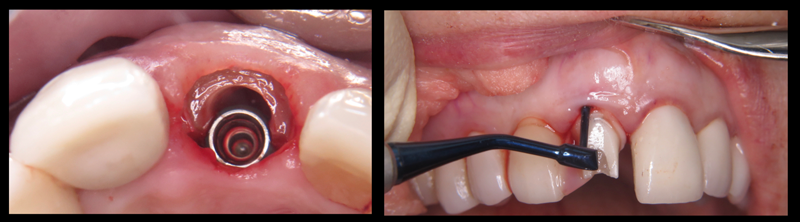

Fig 5. Left panel: Implant was placed,

leaving a gap for the bone graft and abutment. This step is crucial for developing a proper emergence profile. Right panel: The final zirconia

abutment was seated and the bone graft was packed into the gap, preventing tissue migration into the socket.

Figure 5

Fig 6. Immediate cemented

provisional crown. Note the lack of bleeding and healthy gingiva immediately postoperatively. Postoperative radiograph shows partial root,

implant, and zirconia abutment.